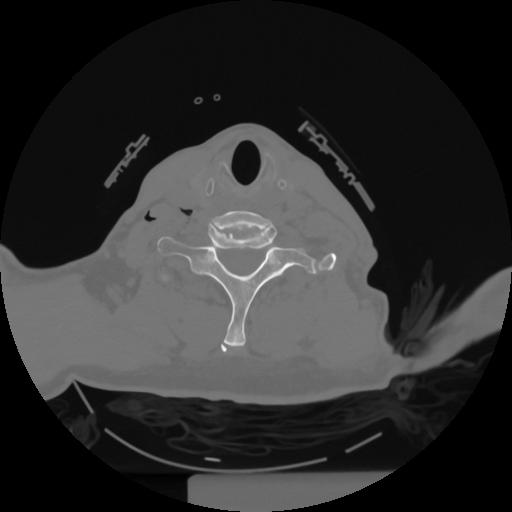

12 P.BLANDAS,,Vol,0.5,P.BLANDAS,,